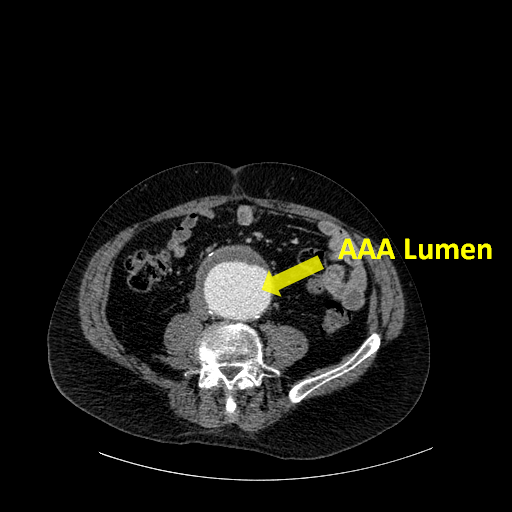

In this paper, we propose a multi-robot manufacturing scheme for flexible production of personalized medical stent grafts. A stent graft, as shown in Fig. 1, is a tubular structure composed of a fabric tube, the graft, supported by multiple metal rings called stents. It is a medical device commonly used during endovascular surgery for treating vascular diseases such as Abdominal Aortic Aneurysms (AAA), a major contributor to cardiovascular related deaths in the Western world [2].

While endovascular repair has been increasingly utilized, there are very few providers of personalized stent grafts [3]. Each personalized stent graft is designed to fit a patient’s specific anatomical structures, e.g. the diameter and length of the aneurysm, obtained from their computed tomography (CT) or magnetic resonance (MR) scans. Similar to tailored garments, most of these personalized devices are handmade, requiring an extensive period of human crafting. The current process can take weeks or even months, subjecting patients to significant risks of deadly aneurysm rupture. Autonomous manufacturing for custom-made stent grafts therefore provides tremendous potential and is an unmet clinical demand.

The shape of the mandrel is customized together with the stent graft to fit to each patient’s anatomy. Fig. 3 illustrates the three stages of designing a stent graft and the corresponding mandrel. Starting from the patient’s CT/MR scan images (Fig. 3a), the 3D geometry of the aorta and the aneurysm is reconstructed (Fig. 3b). A stent graft is hence designed based on this 3D model and the mandrel is designed to be in the same shape, with grooves arranged for positioning the stents and sewing slots for needle piercing. The design specification and the CAD model are stored in a shared repository. This information can be retrieved, for example, via a radio-frequency identification (RFID) tag attached to the 3D printed mandrel (Fig. 2).